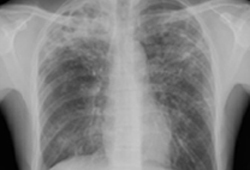

Pulmonary tuberculosis

Pulmonary TB with cavitation

From the personal collection of David Horne and Masahiro Narita; used with permission